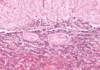

Pars nervosa of pituitary consists of neuropil, pituicytes, endothelial cells, fenestrated capillaries, Herring bodies

Pars nervosa: neuropil is wispy material, most nuclei belong to pituicytes, some endothelial cells near RBC, fenestrated capillaries, identifying feature: pink blob called Herring bodies

Pituitary - Pars nervosa: fenestrated capillary, neuropil, Herring body

Pars nervosa: pituicytes, herring bodies

Pituicyte of pars nervosa

Pars nervosa of pituitary gland